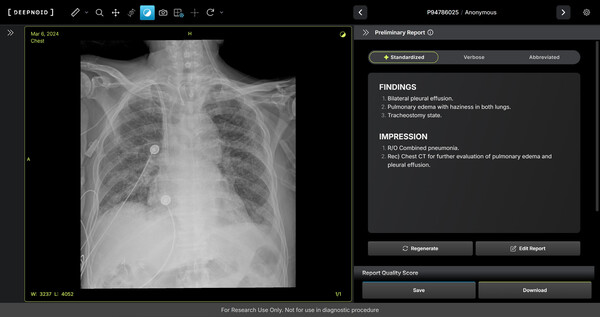

또한 딥노이드(대표 최우식)는 멀티모달 생성형 AI 기반 의료기기 ‘M4CXR’의 핵심 기술 연구를 이번 학술대회에서 구연 발표하며 기술력을 입증했다. M4CXR은 흉부 X-ray 영상의 41종 병변을 판독해 수초 만에 신뢰성 높은 판독소견서 초안을 생성하는 혁신 솔루션이다.

이번 발표에서는 비전-언어 모델을 활용한 이중판독 시스템 연구 결과와 실제 임상 데이터로 검증한 판독소견서 초안의 정량적·정성적 평가 결과가 공개됐다. 현재 다기관 임상시험을 진행 중인 M4CXR은 향후 의료기기 허가와 급여 등재를 통해 상용화에 박차를 가할 계획이다.